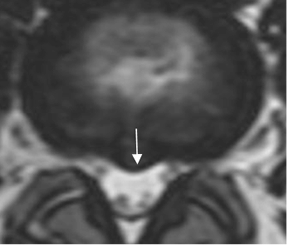

El efecto de masa y la compresión de las raíces nerviosas, no son los únicos responsables de la radiculopatía. La inflamación, factores inmunológicos y cambios vasculares, son factores que contribuyen al dolor. (20). (Fig 82 y 83).

Fig 82. Efecto de hernia.

RM axial en T2. Prominencia asimétrica sin contacto con las raíces y que ¨teóricamente¨, no debe ocasionar síntomas.